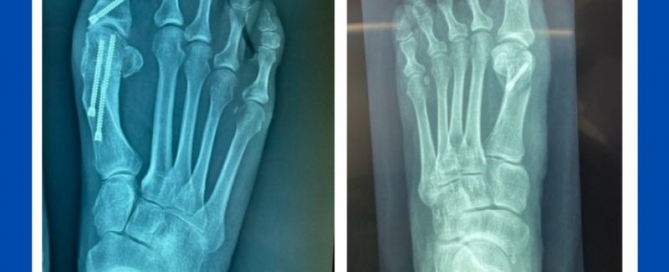

Biomechanics of a pathology (bunions and pes planus)

Blog's main page This is a great example of how poor biomechanics impacts foot pathology. This is a case of juvenile bunions with flat feet that has recently been presented [...]